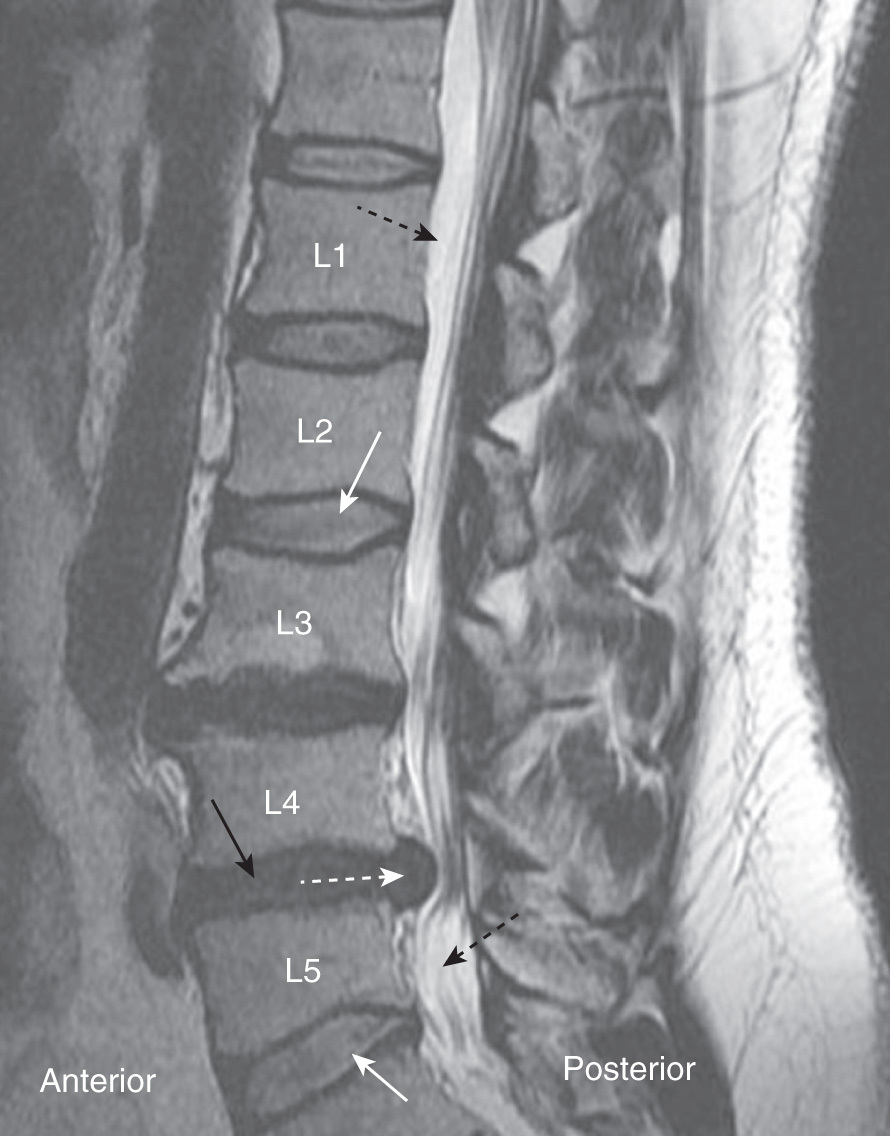

What is going on in this spine MRI?

The L4-L5 disc has herniated!